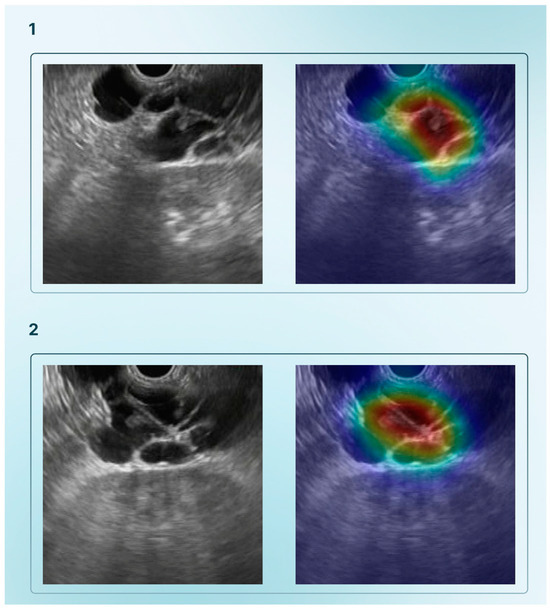

| Tonozuka et al., 2021 [27] | Detect PDAC from EUS images using a DL model | 1 | NK | 1390 static images (with data augmetation 88,320) | NK | CNN and pseudocolored heatmap | Frame labelling of all datasets (PDAC, CP, or NP) | Train–validation–test (training–validation set ratio: 90–10%; 10-fold cross–validation) | PDAC, CP, NP | 92.4% | 84.1% | 0.940 |

| Saraiva et al., 2024 [15] | Develop a CNN for detecting and distinguish PCN (namely M-PCN and NM-PCN) and PSL (PDAC and PNET) | 4 | 378 | 126,000 | M-PCN: 19,528; NM-PCN: 8175; PDAC: 64,286; PNET 29,153 | ResNet | Each image had a predicted classification related to the highest probability | Train–test split (90–10%) | M-PCN; NM-PCN; PDAC; PNET; NP | M-PCN: 98.9% NM-PCN: 99.3% PDAC:98.7% PNET:83.7% | M-PCN: 99.1% NM-PCN: 99.9% PDAC: 83.7% PNET: 98.7% | NK |